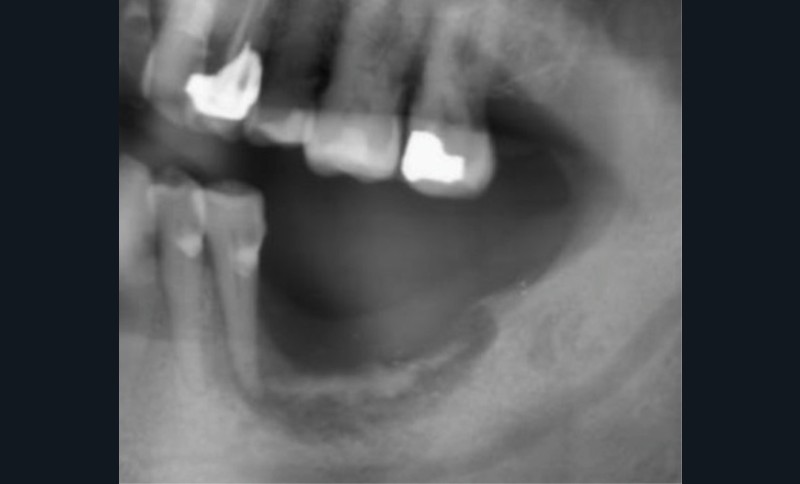

Le principal risque d’ostéonécrose en lien avec une biothérapie est dû à l’inhibiteur du RANKL, le dénosumab (commercialisé sous le nom de Xgeva® en indication oncologique, Prolia® en indication rhumatologique) (fig. 1). Cet anticorps bloque la liaison du RANKL à son récepteur, qui permet notamment l’activation des ostéoclastes. La résorption osseuse est alors bloquée, action intéressante dans le cadre d’une ostéoporose ou de métastases osseuses. Cependant, même si le mécanisme d’action est totalement différent, on retrouve les mêmes effets indésirables que ceux observés avec les bisphosphonates au niveau de la cavité orale. Les patients traités par anti-RANKL présenteront un risque d’ostéonécrose des mâchoires. Ce risque sera évidemment plus ou moins important en fonction de facteurs à rechercher : indication du traitement (oncologique ou rhumatologique), durée totale du traitement, date de dernière administration, corticothérapie associée, diabète, présence de foyers infectieux bucco-dentaires…

Dans le bilan avant mise en place du traitement, les recommandations, notamment de rhumatologie, indi-quent la réalisation d’un bilan dentaire et la mise en œuvre des soins nécessaires [1]. Cela a pour but d’identifier les foyers infectieux en présence et de les prendre en charge avant que le traitement ne débute, donc avant que le patient présente un risque infectieux accru (fig. 2).